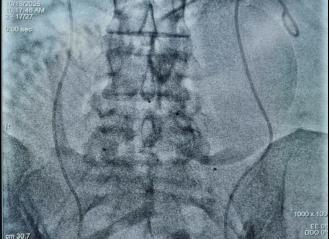

动脉球囊阻断术辅助前置胎盘手术临床应用(2019年9月开始我院第一例手术)

治疗效果确切疾病:中央性前置胎盘、胎盘植入